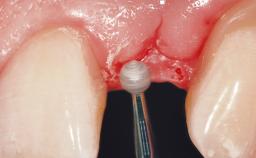

Early Placement of an Implant in a Maxillary Right Central Incisor Site

This 41-year-old female patient was referred to the clinic for the replacement of the right central incisor, since the tooth had developed a root fracture in the long axis that made extraction necessary. The healthy, non-smoking patient was first seen with the tooth still in place. A detailed Esthetic Risk Assessment was performed.The patient was worried about her dental esthetics and had high expectations for a successful treatment outcome from an esthetic point of view. The patient had a medium lip line that displayed parts of the gingiva in the anterior maxilla upon smile.

Soft Tissue Anatomy Intact Defective

Bone Volume Horizontally and vertically sufficient Horizontally deficient Deficient vertically or deficient vertically AND horizontally